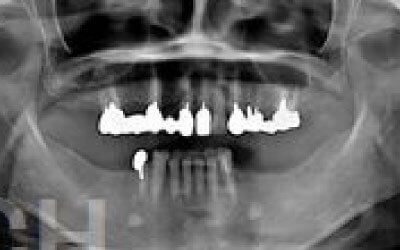

ブリッジとインプラントでは、前後の歯の寿命に大きな違いがあります。ブリッジでは、支えとなる歯を虫歯がなくても大きく削る必要があり、さらに噛む力が通常の1.5倍かかるため、その寿命が短くなりがちです。実際の統計によると、ブリッジの支えとなる歯の68%が、10年以内に抜歯を余儀なくされるという結果が出ています。

噛むとき、誰でも歯に何十キロもの力がかかっています。当然、歯の本数が減れば減るほど、残った歯にかかる負担は大きくなります。ブリッジ治療の場合、失われた歯にかかっていた力は、前後の歯で支えることになります。その結果、残った歯には、抜歯していないときに比べて1.5〜2倍程度の力がかかることになります。

ブリッジなどの治療では、前後の歯を大きく削る必要があります。場合によっては、虫歯がないのに歯の神経を取らなければならないこともあります。実際、神経を取って被せ物をすると、その歯は一気に「最終段階」に進んでしまうのです。しかし、インプラント治療では、前後の歯を削ることも、神経を取ることもありません。歯の寿命を延ばすためにも、健康な歯をできるだけ削らないことが非常に重要なのです。

最も大きな違いは、前後の歯の寿命に影響が出ることです。

ブリッジの場合、抜けた部分の前後の歯を大きな虫歯と同じくらい削る必要があります。

また、抜けた歯の力を前後の歯が支えているため、ブリッジを支える歯には常に1.5倍の負担がかかることになります。

1)ブリッジ

2)歯を大きく削る+支えの歯に1.5倍の力がかかる

3)前後の歯の寿命が著しく減る

ブリッジの支えの歯は、データでは10年以内に68%が抜歯になります。